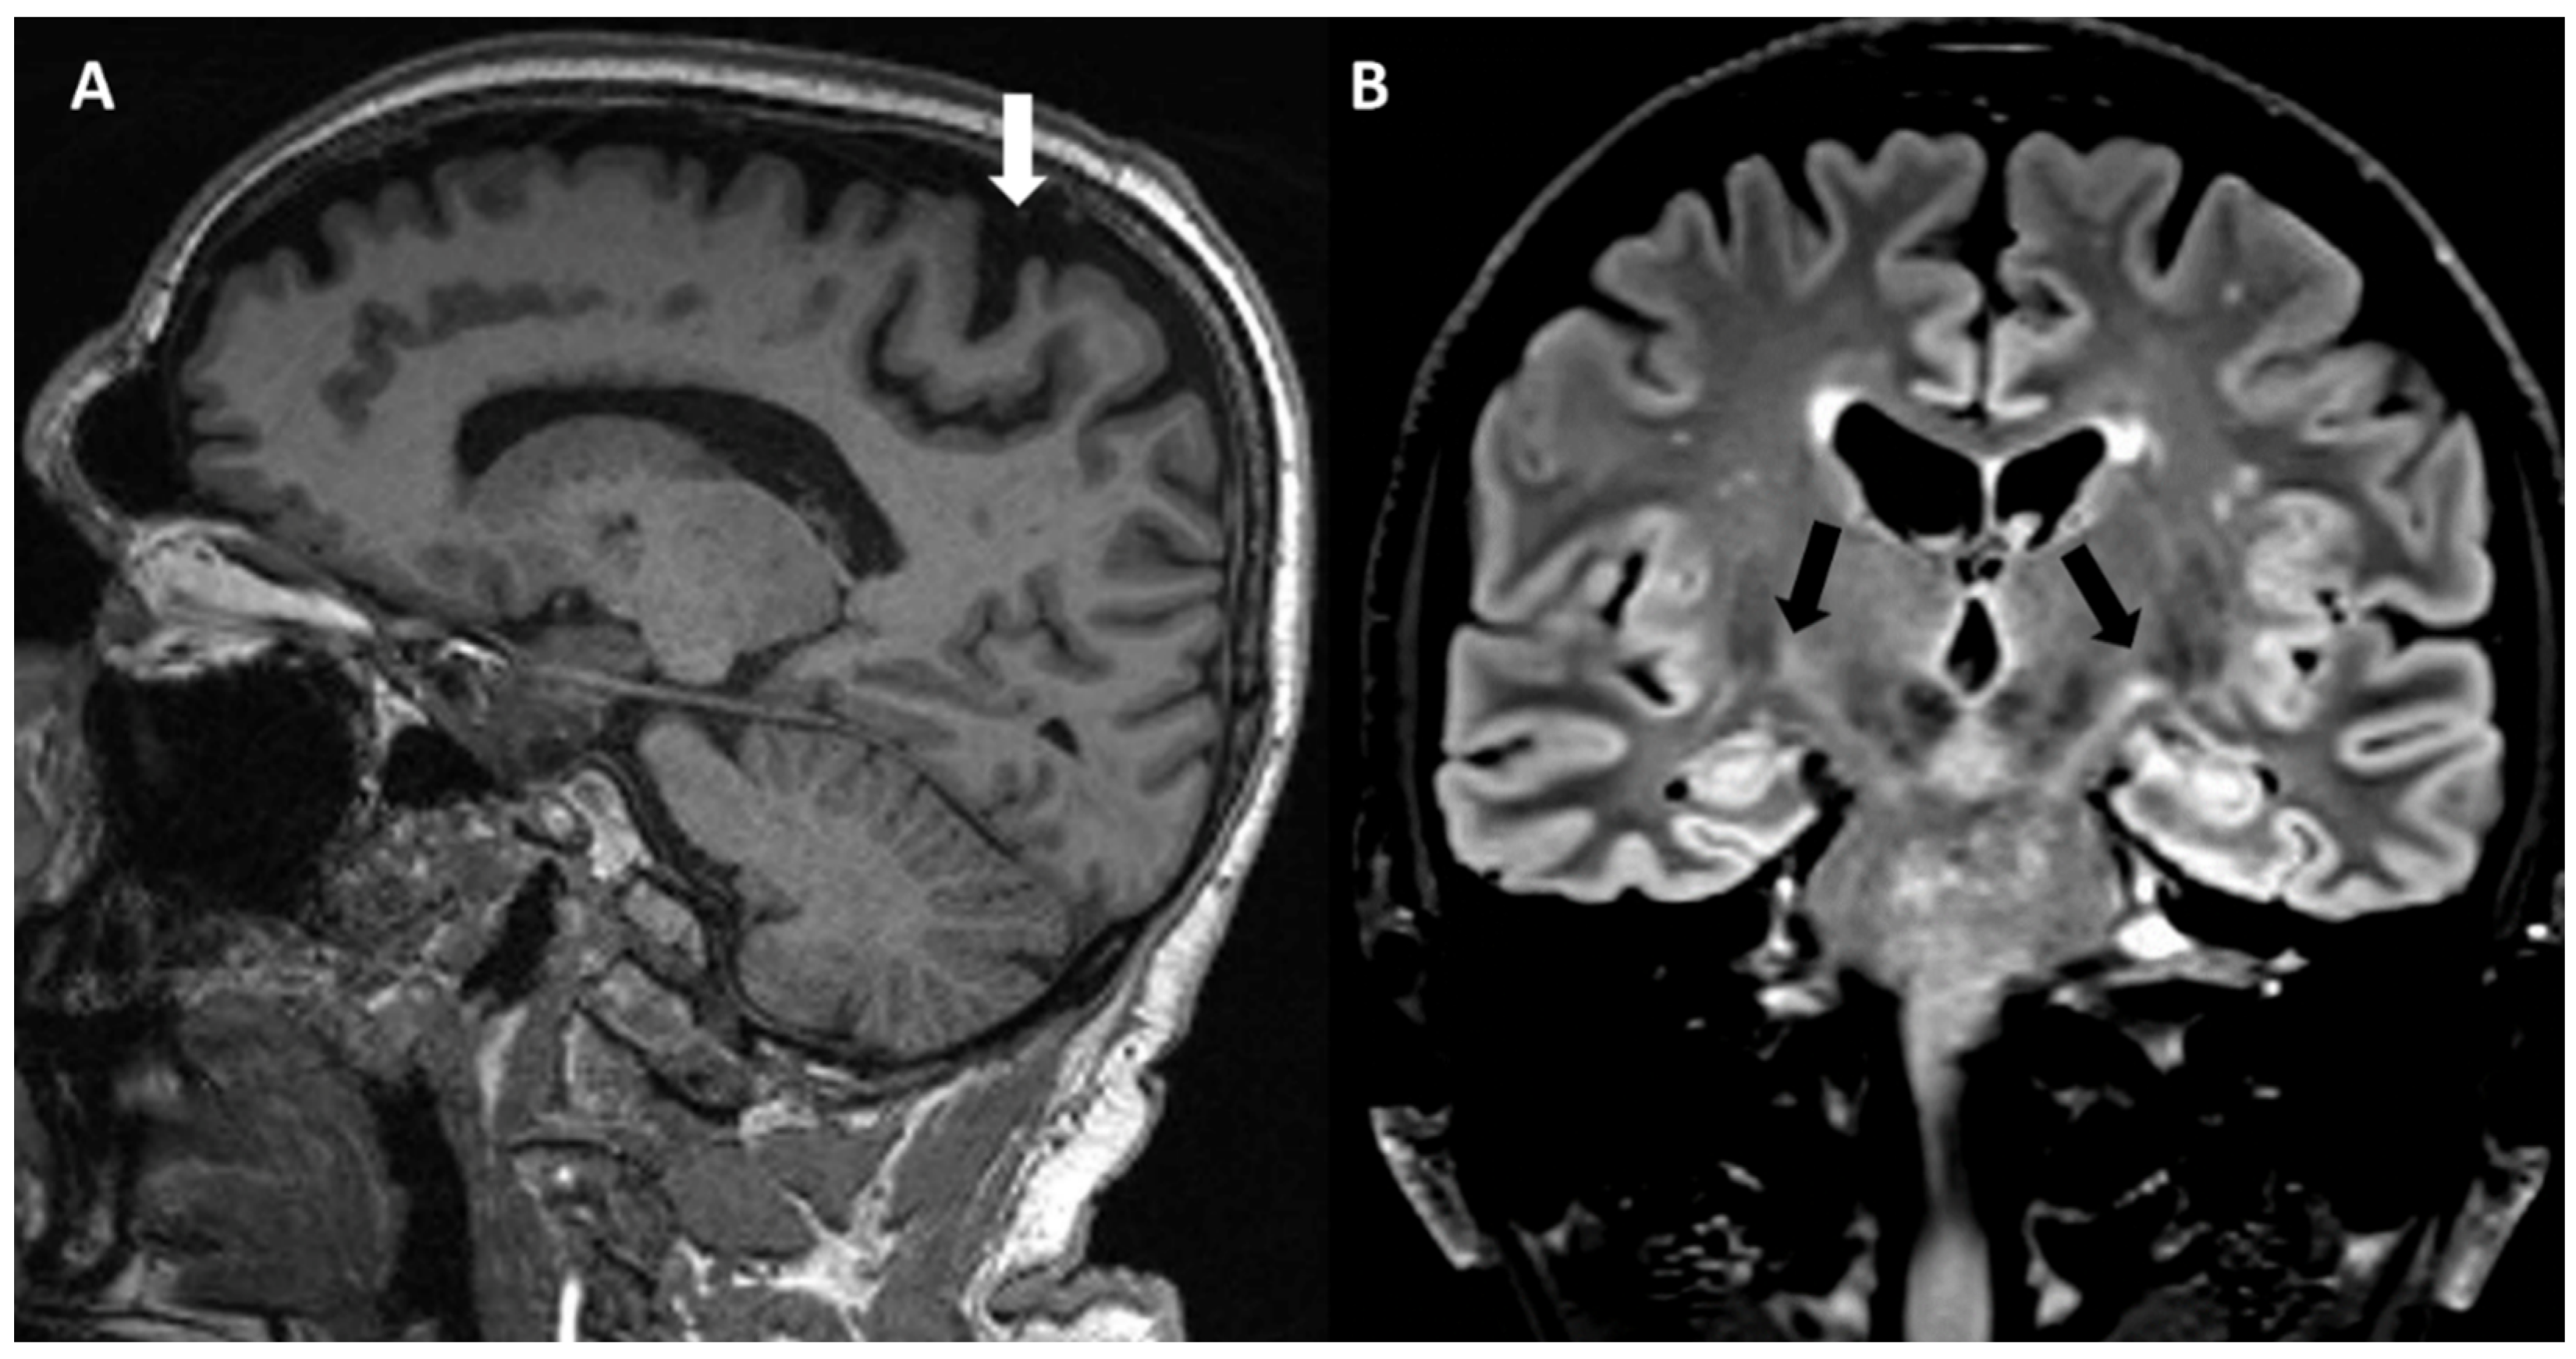

- Pioro, E.P.; Turner, M.R.; Bede, P. Neuroimaging in primary lateral sclerosis. Amyotroph. Lateral Scler. Front. Degener. 2020, 21, 18–27. [Google Scholar] [CrossRef]

- Smith, C.D. Serial MRI findings in a case of primary lateral sclerosis. Neurology 2002, 58, 647–649. [Google Scholar] [CrossRef]

- Martı-Fabregas, J.; Pujol, J. Selective involvement of the pyramidal tract on magnetic resonance imaging in primary lateral sclerosis. Neurology 1990, 40, 1799–1800. [Google Scholar] [CrossRef]

- Mascalchi, M.; Salvi, F.; Valzania, F.; Marcacci, G.; Bartolozzi, C.; Tassinari, C.A. Corticospinal tract degeneration in motor neuron disease. AJNR Am. J. Neuroradiol. 1995, 16, 878–880. [Google Scholar]

- Paliwal, V.K.; Rahi, S.K.; Singh, P.; Gupta, R.K. “Wine-glass appearance” of pyramidal tracts in a patient with primary lateral sclerosis. Neurol. India 2012, 60, 110–111. [Google Scholar] [CrossRef]

- Chung, H.S.; Melkus, G.; Bourque, P.; Chakraborty, S. Motor Band Sign in Motor Neuron Disease: A Marker for Upper Motor Neuron Involvement. Can. J. Neurol. Sci. 2023, 50, 373–379. [Google Scholar] [CrossRef]

- Rizzo, G.; Marliani, A.F.; Battaglia, S.; Albini Riccioli, L.; De Pasqua, S.; Vacchiano, V.; Infante, R.; Avoni, P.; Donadio, V.; Passaretti, M.; et al. Diagnostic and Prognostic Value of Conventional Brain MRI in the Clinical Work-Up of Patients with Amyotrophic Lateral Sclerosis. J. Clin. Med. 2020, 9, 2538. [Google Scholar] [CrossRef]